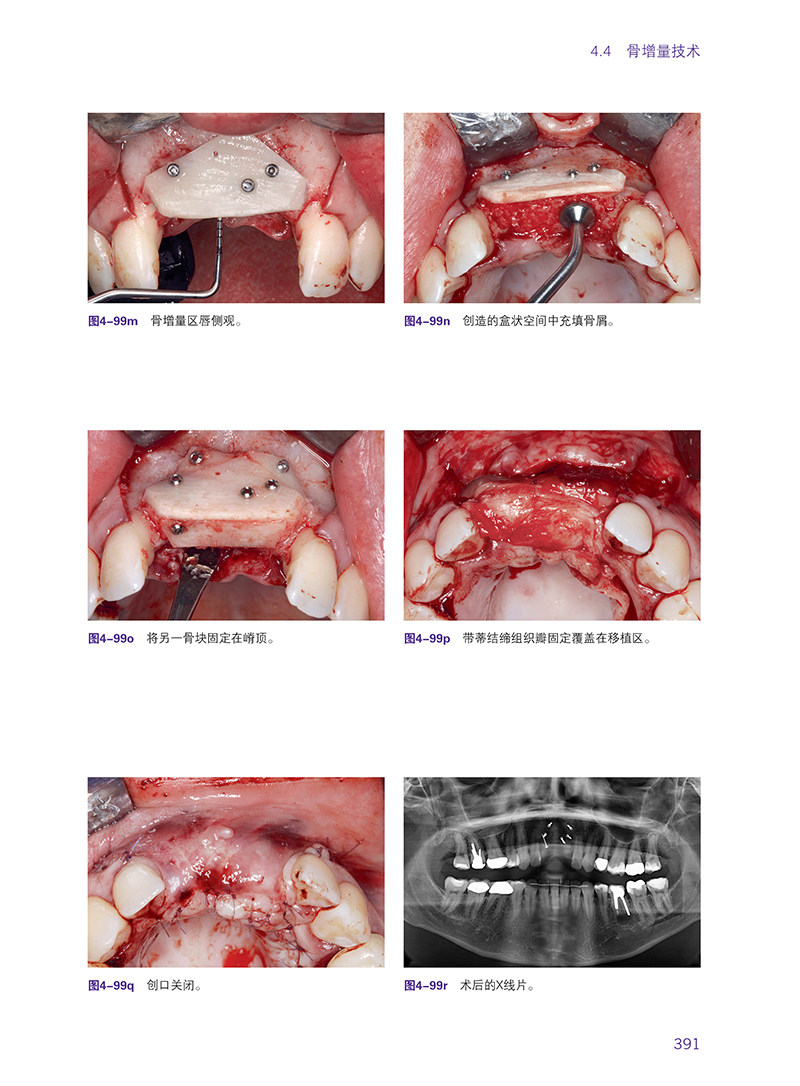

书名:口腔种植软硬组织增量自体组织移植技术

作者:(德)福阿德.库里

出版社名称:辽宁科学技术出版社

出版日期:2023年6月